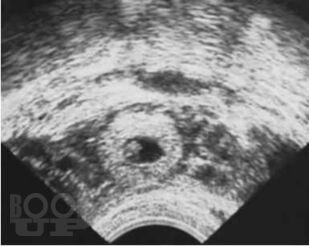

Внематочная беременность

В пособии представлены данные об этиологии, современных методах диагностики и лечения внематочной беременности. Подробно изложен алгоритм обследования при внематочной беременности на различных этапах постановки диагноза, тактика ведения пациенток. В результате использования учебного пособия студенты могут овладеть следующими компетенциями: ОПК 8, 11, 12; ПК 1, 5, 6, 8, 9, 10. Предназначено для подготовки студентов IV, V курсов лечебного факультета к занятиям семинарского типа по дисциплине «Акушерство и гинекология» и составлено с учетом требований ФГОС 3++ по направлению специальности «Лечебное дело».